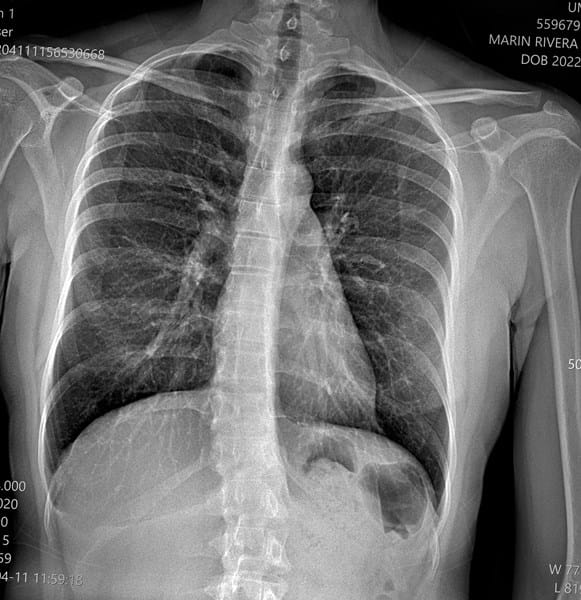

¿Mi escoliosis es leve o moderada. Cuales son los grados

Hola quiero saber de cuantos grados es mi escoliosis si es leve o moderada y como puedo corregirla cual es el tratamiento

Hola esta es otra radiografía tengo 20 años he estado haciendo ejercicios para la escoliosis, pero no se si con los ejercicios mejore por favor usted viendo más o menos la radiografía cree que sea moderada o leve

I. Hola Compañera, le agradezco el voto de confianza pero por desgracia no tengo ninguna formación para poder opinar a ese nivel -ni a ninguno en realidad-, pero mi punto de vista personal, aunque sea desde la ignorancia, es que su escoliosis es moderada, no leve.

Sin embargo, según estoy leyendo y viendo, estaría equivocado, su escoliosis se enmarca más bien en un nivel leve, o a lo sumo intermedio entre leve y moderada,

El tipo de escoliosis que padece, pienso sería de clase torácico-lumbar, (más bien torácica según este esquema) dado que, simplificando mucho, existen hasta cuatro tipos de esta,